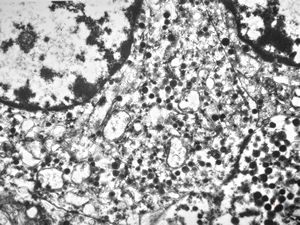

F, 71y. | carcinoid … metastasis to lymphonode